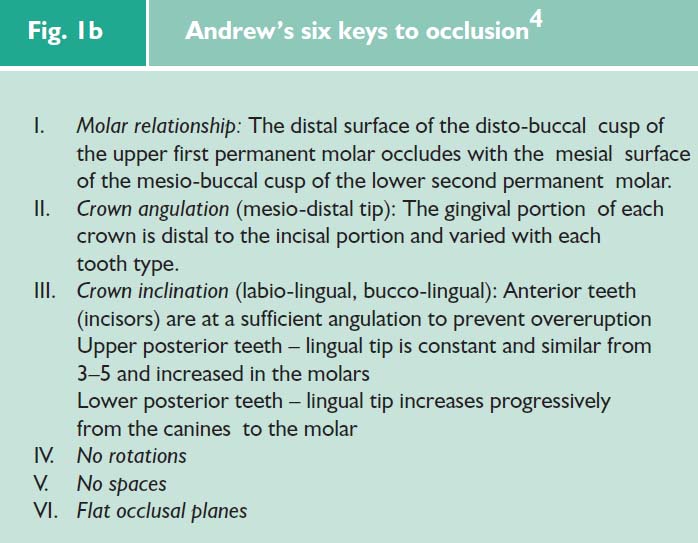

There is no doubt that the introduction of, firstly the six keys philosophy (Fig. 1b), and secondly, the pre-adjusted edgewise appliance designed to achieve them was a quantum leap for orthodontists.

Unfortunately, there is no evidence that achieving this ‘optimal’ occlusion has any influence upon long-term stability, masticatory function or the alleged association between orthodontic treatment and temporomandibular disorders.

The prime reason for a patient to seek orthodontic treatment is to gain an improvement in appearance. Arguably, we should primarily aim to treat the patient’s needs rather than pursue a dogmatic adherence to the six keys of occlusion.